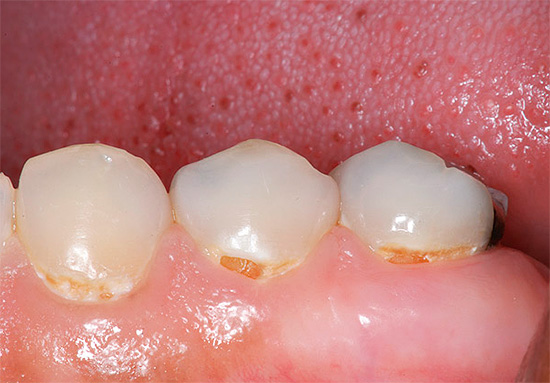

A foto a seguir mostra claramente a cárie profunda na região cervical:

A cárie cervical média e profunda é frequentemente caracterizada por toda uma paleta de sintomas de dor de todos os tipos de substâncias irritantes. Às vezes, eles podem se juntar à dor causada por influências mecânicas, quando a comida dura entra, mas isso é raro devido ao formato dos dentes, que protege as zonas cervicais dos alimentos que caem sob a borda da gengiva.

Cervical cárie dos dentes anteriores freqüentemente causa dor ao inalar ar frio.